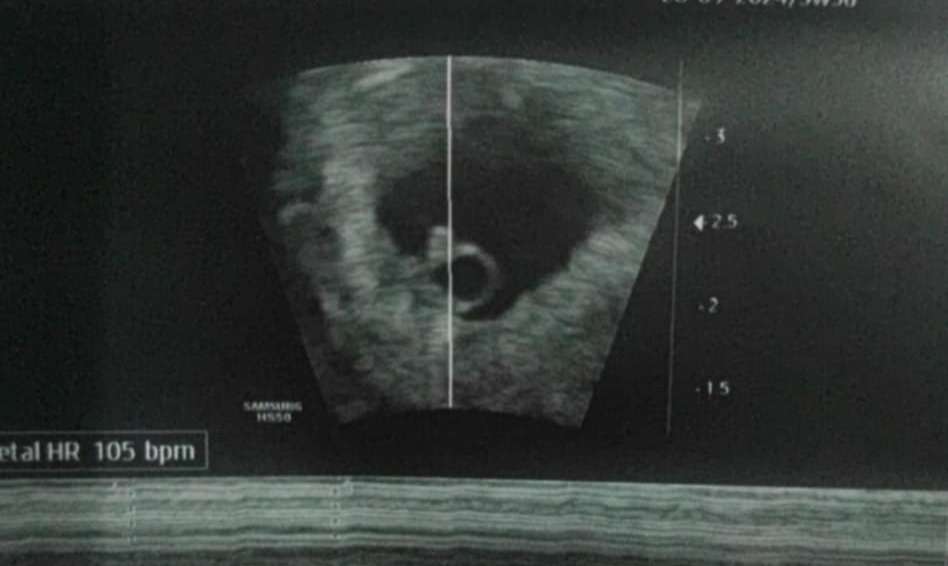

I takie jeszcze, zarodek 3.87 mm